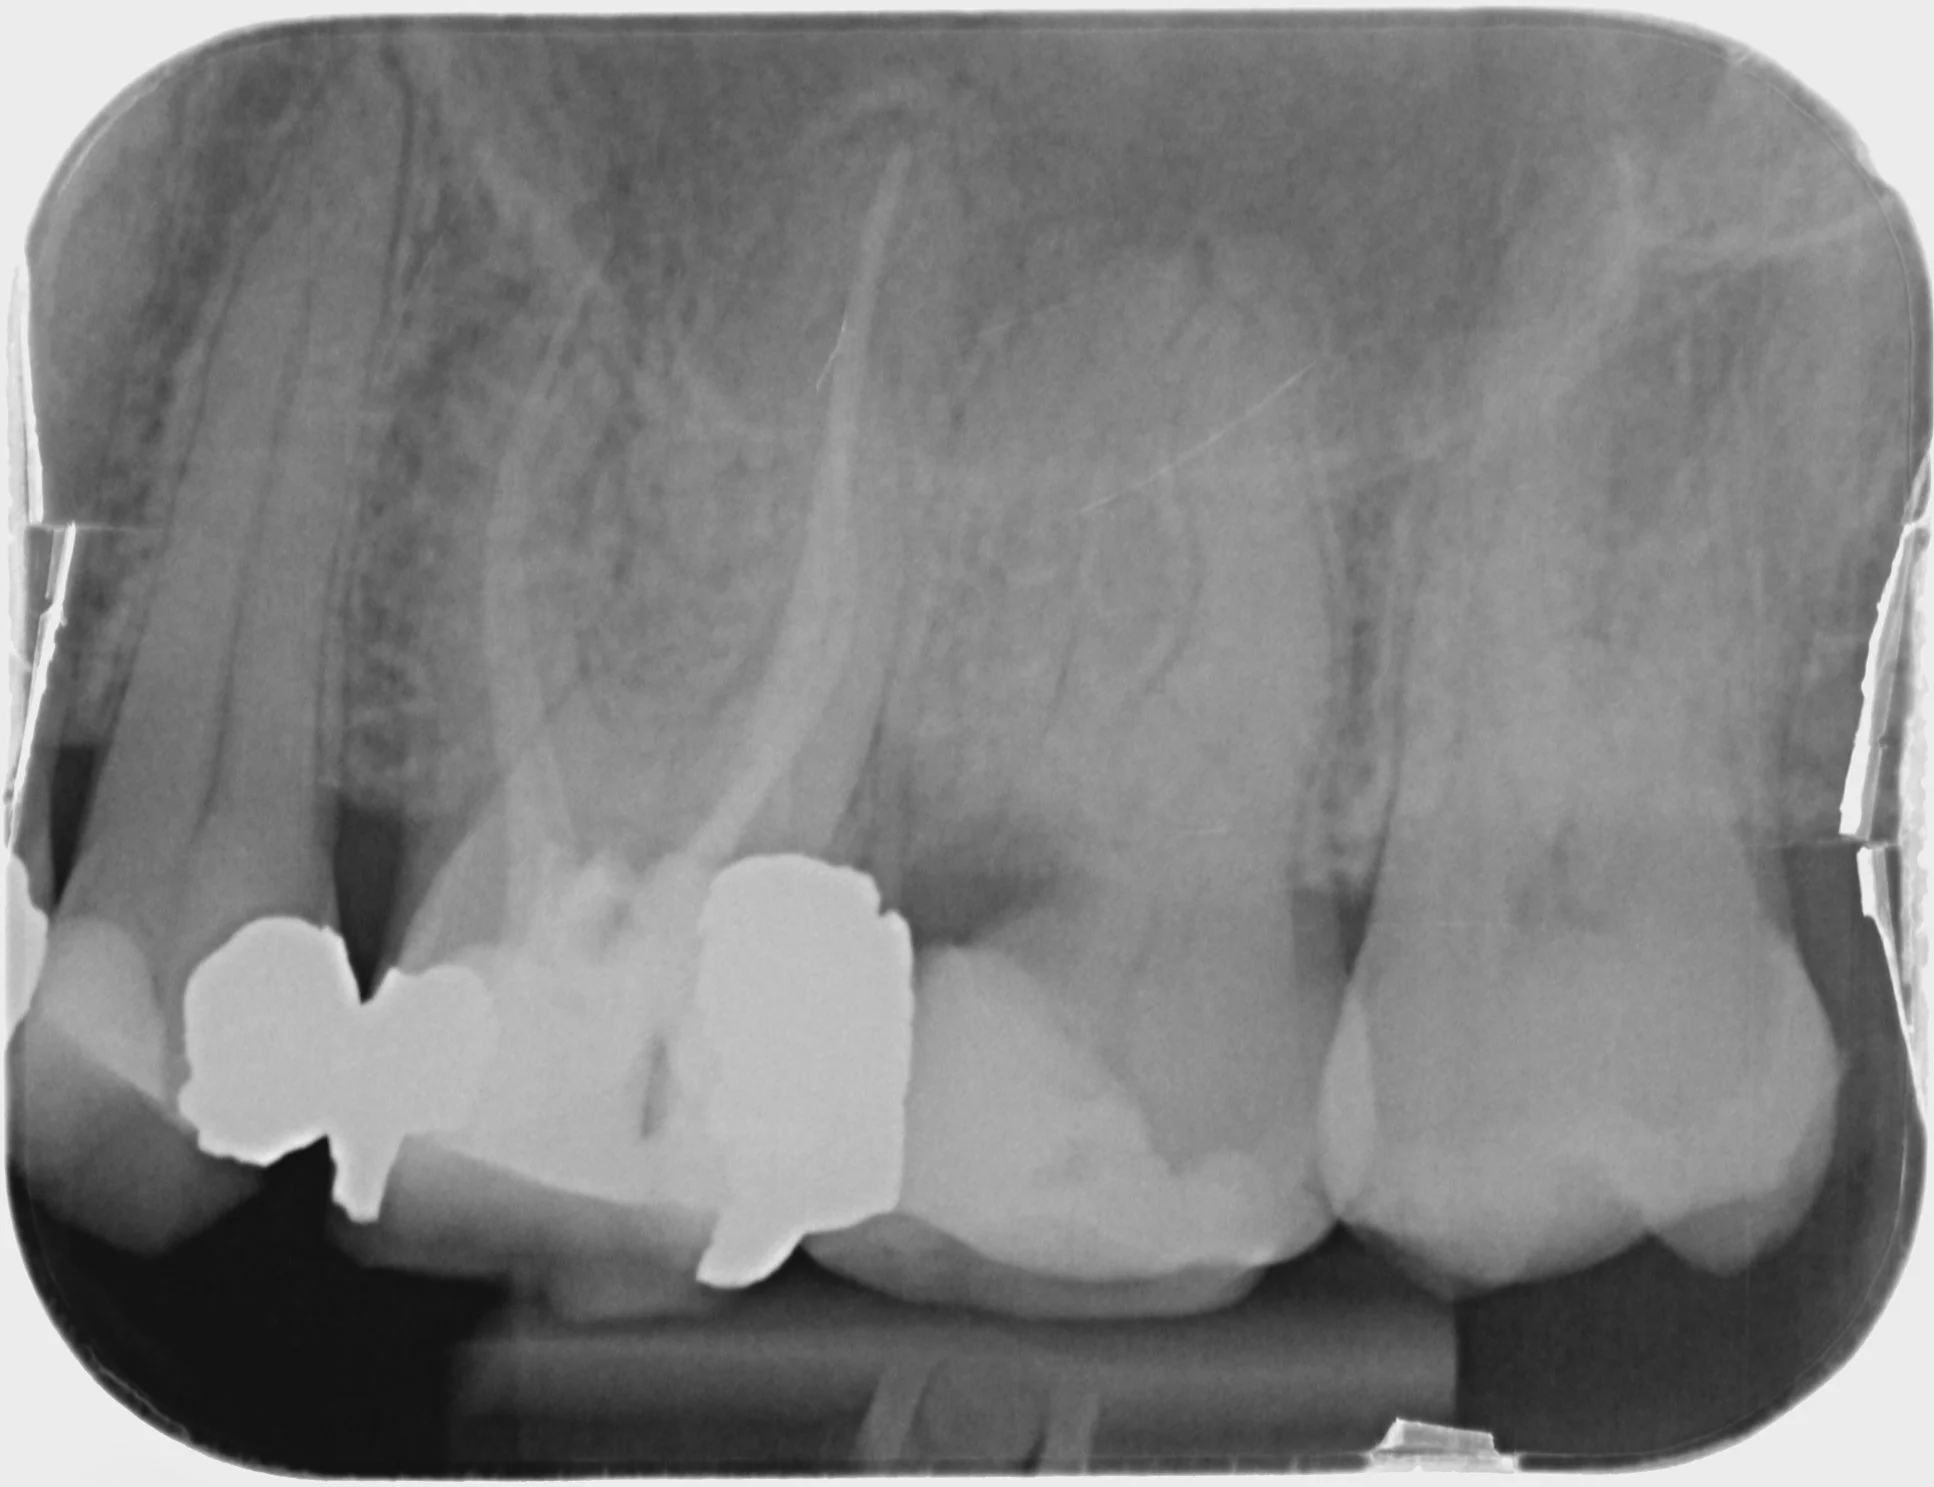

Endodontics